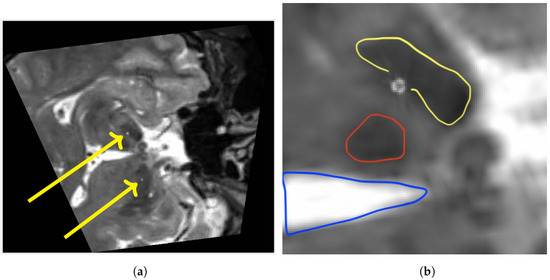

Figure 4.

Fused image after multiplanar reformation (MPR): The images are displayed in accordance with scientific convention. Preoperative T2-weighted MRI (a), and cutout view of the same slice (b). Characteristic hypointensities depicting both the right subthalamic (yellow) and red nucleus (red) as well as the third ventricle (blue) on preoperative T2-weighted MRI. Each segmented contact point can be identified within the anatomical target area.

All images were registered with high precision. The quantitative evaluation yielded an average mean TRE of 1.48 mm over all subjects. Choosing the landmarks carefully took approximately 7.5 min per patient. The intensity-based final registration took 5 s. Table 1 gives an overview of the mean TRE, standard deviation and spatial information. After registration, an MPR along an electrode-based normal vector was computed using a custom Matlab code. Figure 4 shows an exemplary MPR for the right electrode. The segmented contacts appear in the right anatomical structure (STN). Accordingly Figure 5 shows a non-angulated sagittal view where the contacts, as well as the marker, are clearly delineated.